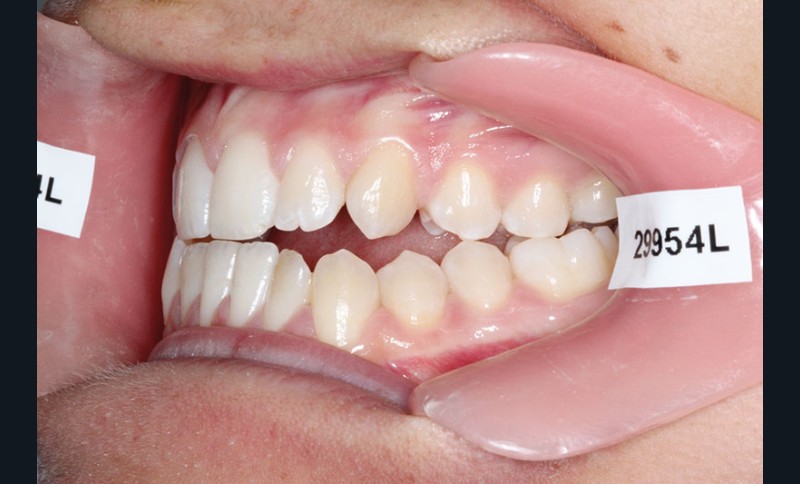

1re phase : recul des secteurs latéraux mandibulaires avec le Motion Classe III Carriere (fig. 4 à 6)

Nous mettons en place des bras latéraux Motion associés à des élastiques intermaxillaires ancrés sur des brackets sur 17 et 27 et une gouttière thermoformée maxillaire portée jour et nuit :

• 1er mois : élastiques 6 oz. 1/4”

• 2e mois et suivants : élastiques 6 oz.1/4“

L’objectif de cette étape est d’obtenir un recul des secteurs latéraux mandibulaires afin de positionner les molaires et canines en classe I et de réorienter le plan d’occlusion en haut en avant.